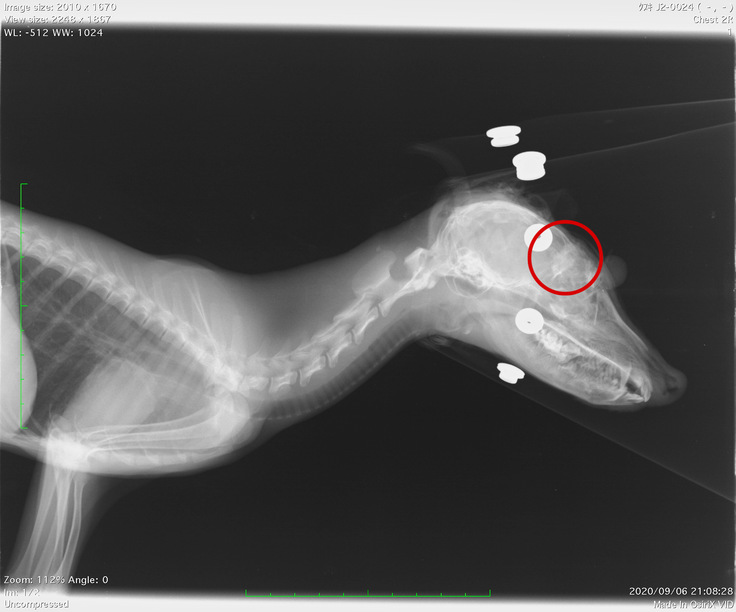

○視覚・聴覚が弱いホンドタヌキ

保護当初、この子は顔面を中心に咬傷があり、右目が脱落した状態でした。当時は命も危ぶまれましたが、集中治療を経て何とか危険を乗り越えてくれました。

咬傷の具合から、恐らくアライグマに襲われたものではないかと推測されます。

残った目も眼球が傷付いていた為、弱視はありますが、現在は日常生活には問題ない程に回復しています。